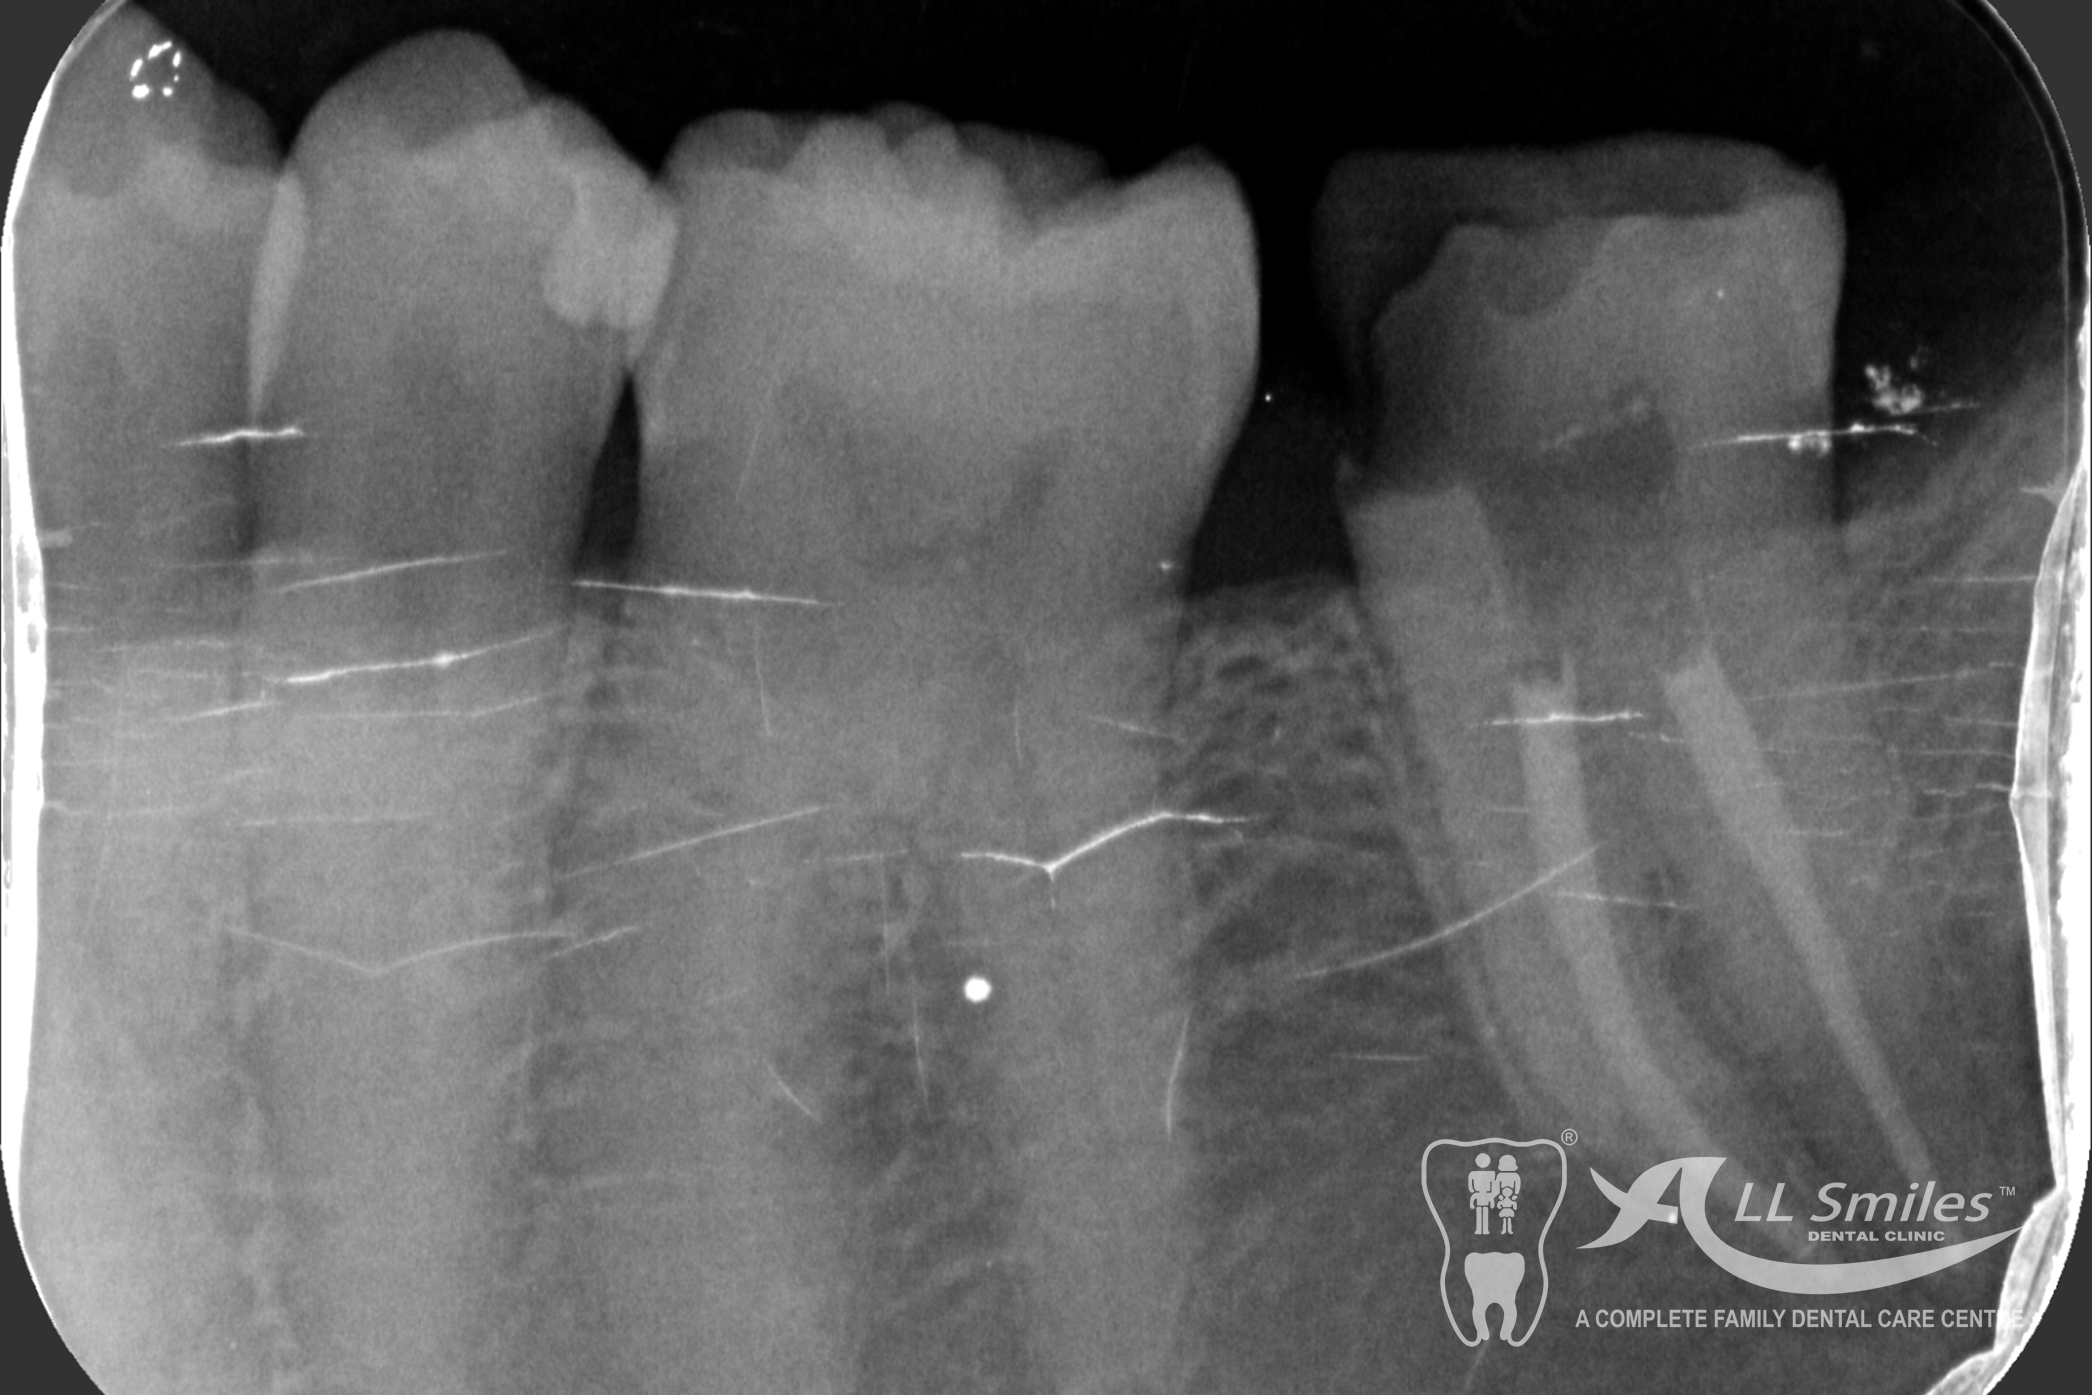

Root Canal Gallery